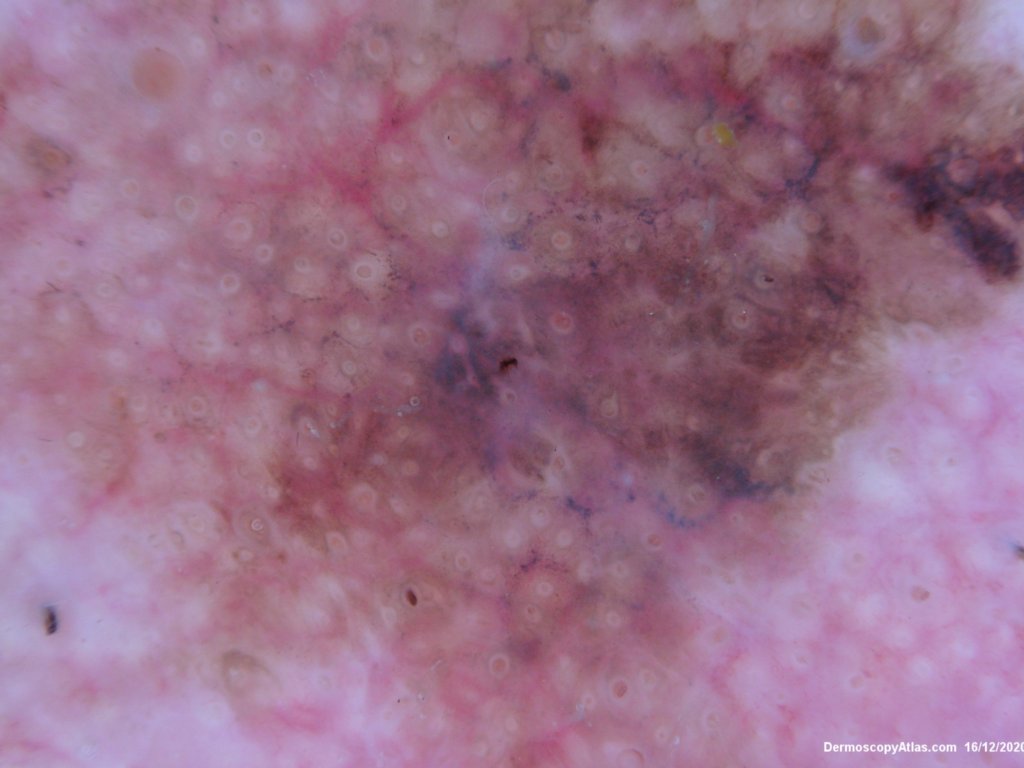

Site: Cheek

Diagnosis: Lentigo Maligna

Description: Pigmented lesion cheek and pink nodule

Elderly male with no past history of melanoma developed these two lesions over a year or so. The lentigo maligna was easy to diagnose on the clinical and dermatoscopy but the nodule was more difficult. Was it an amelanotic melanoma, BCC or SCC were the initial thoughts. Histology showed a well differentiated sebaceous carcinoma. The two lesions were excised in the same specimen with 5 mm margins. Studies failed to show the mutation for the Muir Torre syndrome which can be seen with sebaceous carcinoma.